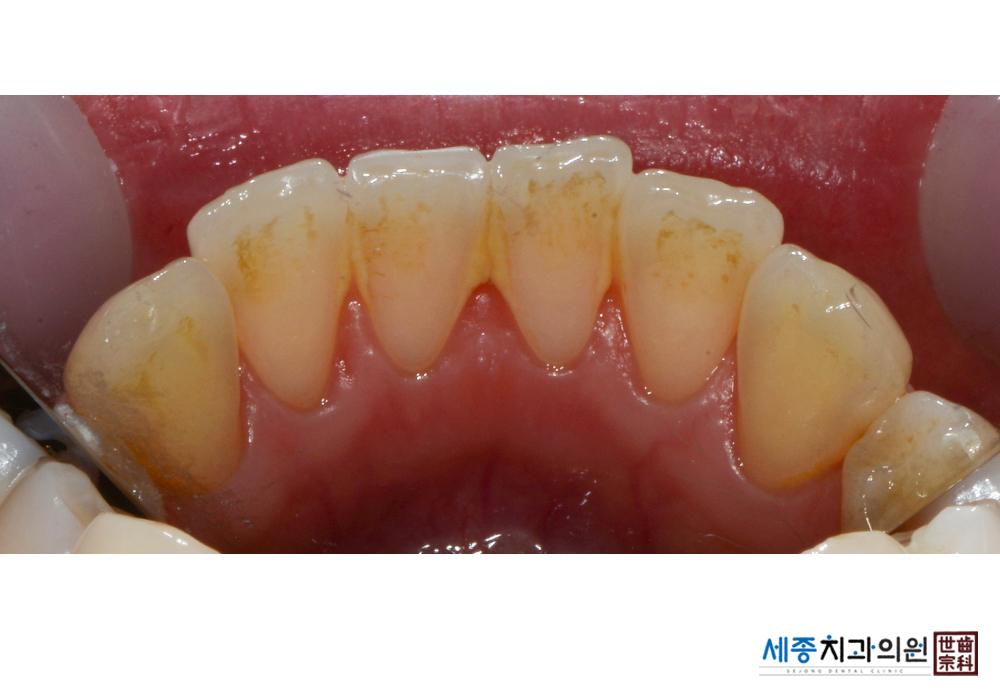

[스케일링] 치주질환 예방 스케일링 치료

치료전 : 2019-01-15

가글마취&저주파 스켈러를 사용한 스케일링